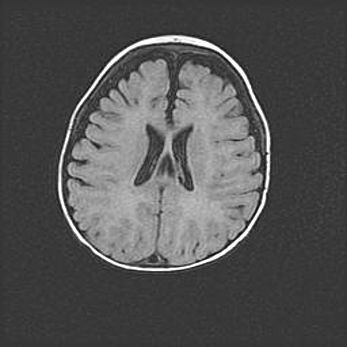

Открытая гидроцефалия.

Возраст: 9 месяцев 12 дней

Вес: 6800 г

Пол: мужской

Окружность головы: 41,5 см

Срок гестации: 28 недель

Гидроцефалия головного мозга у новорожденных имеет характерный признак: опережающий рост окружности головы приводит к визуально хорошо определяемой гидроцефальной форме сильно увеличенного в объёме черепа. Детские неврологи определяют следующие симптомы гидроцефалии у грудничков: выбухающий напряжённый родничок, частое запрокидывание головы, смещение глазных яблок к низу.